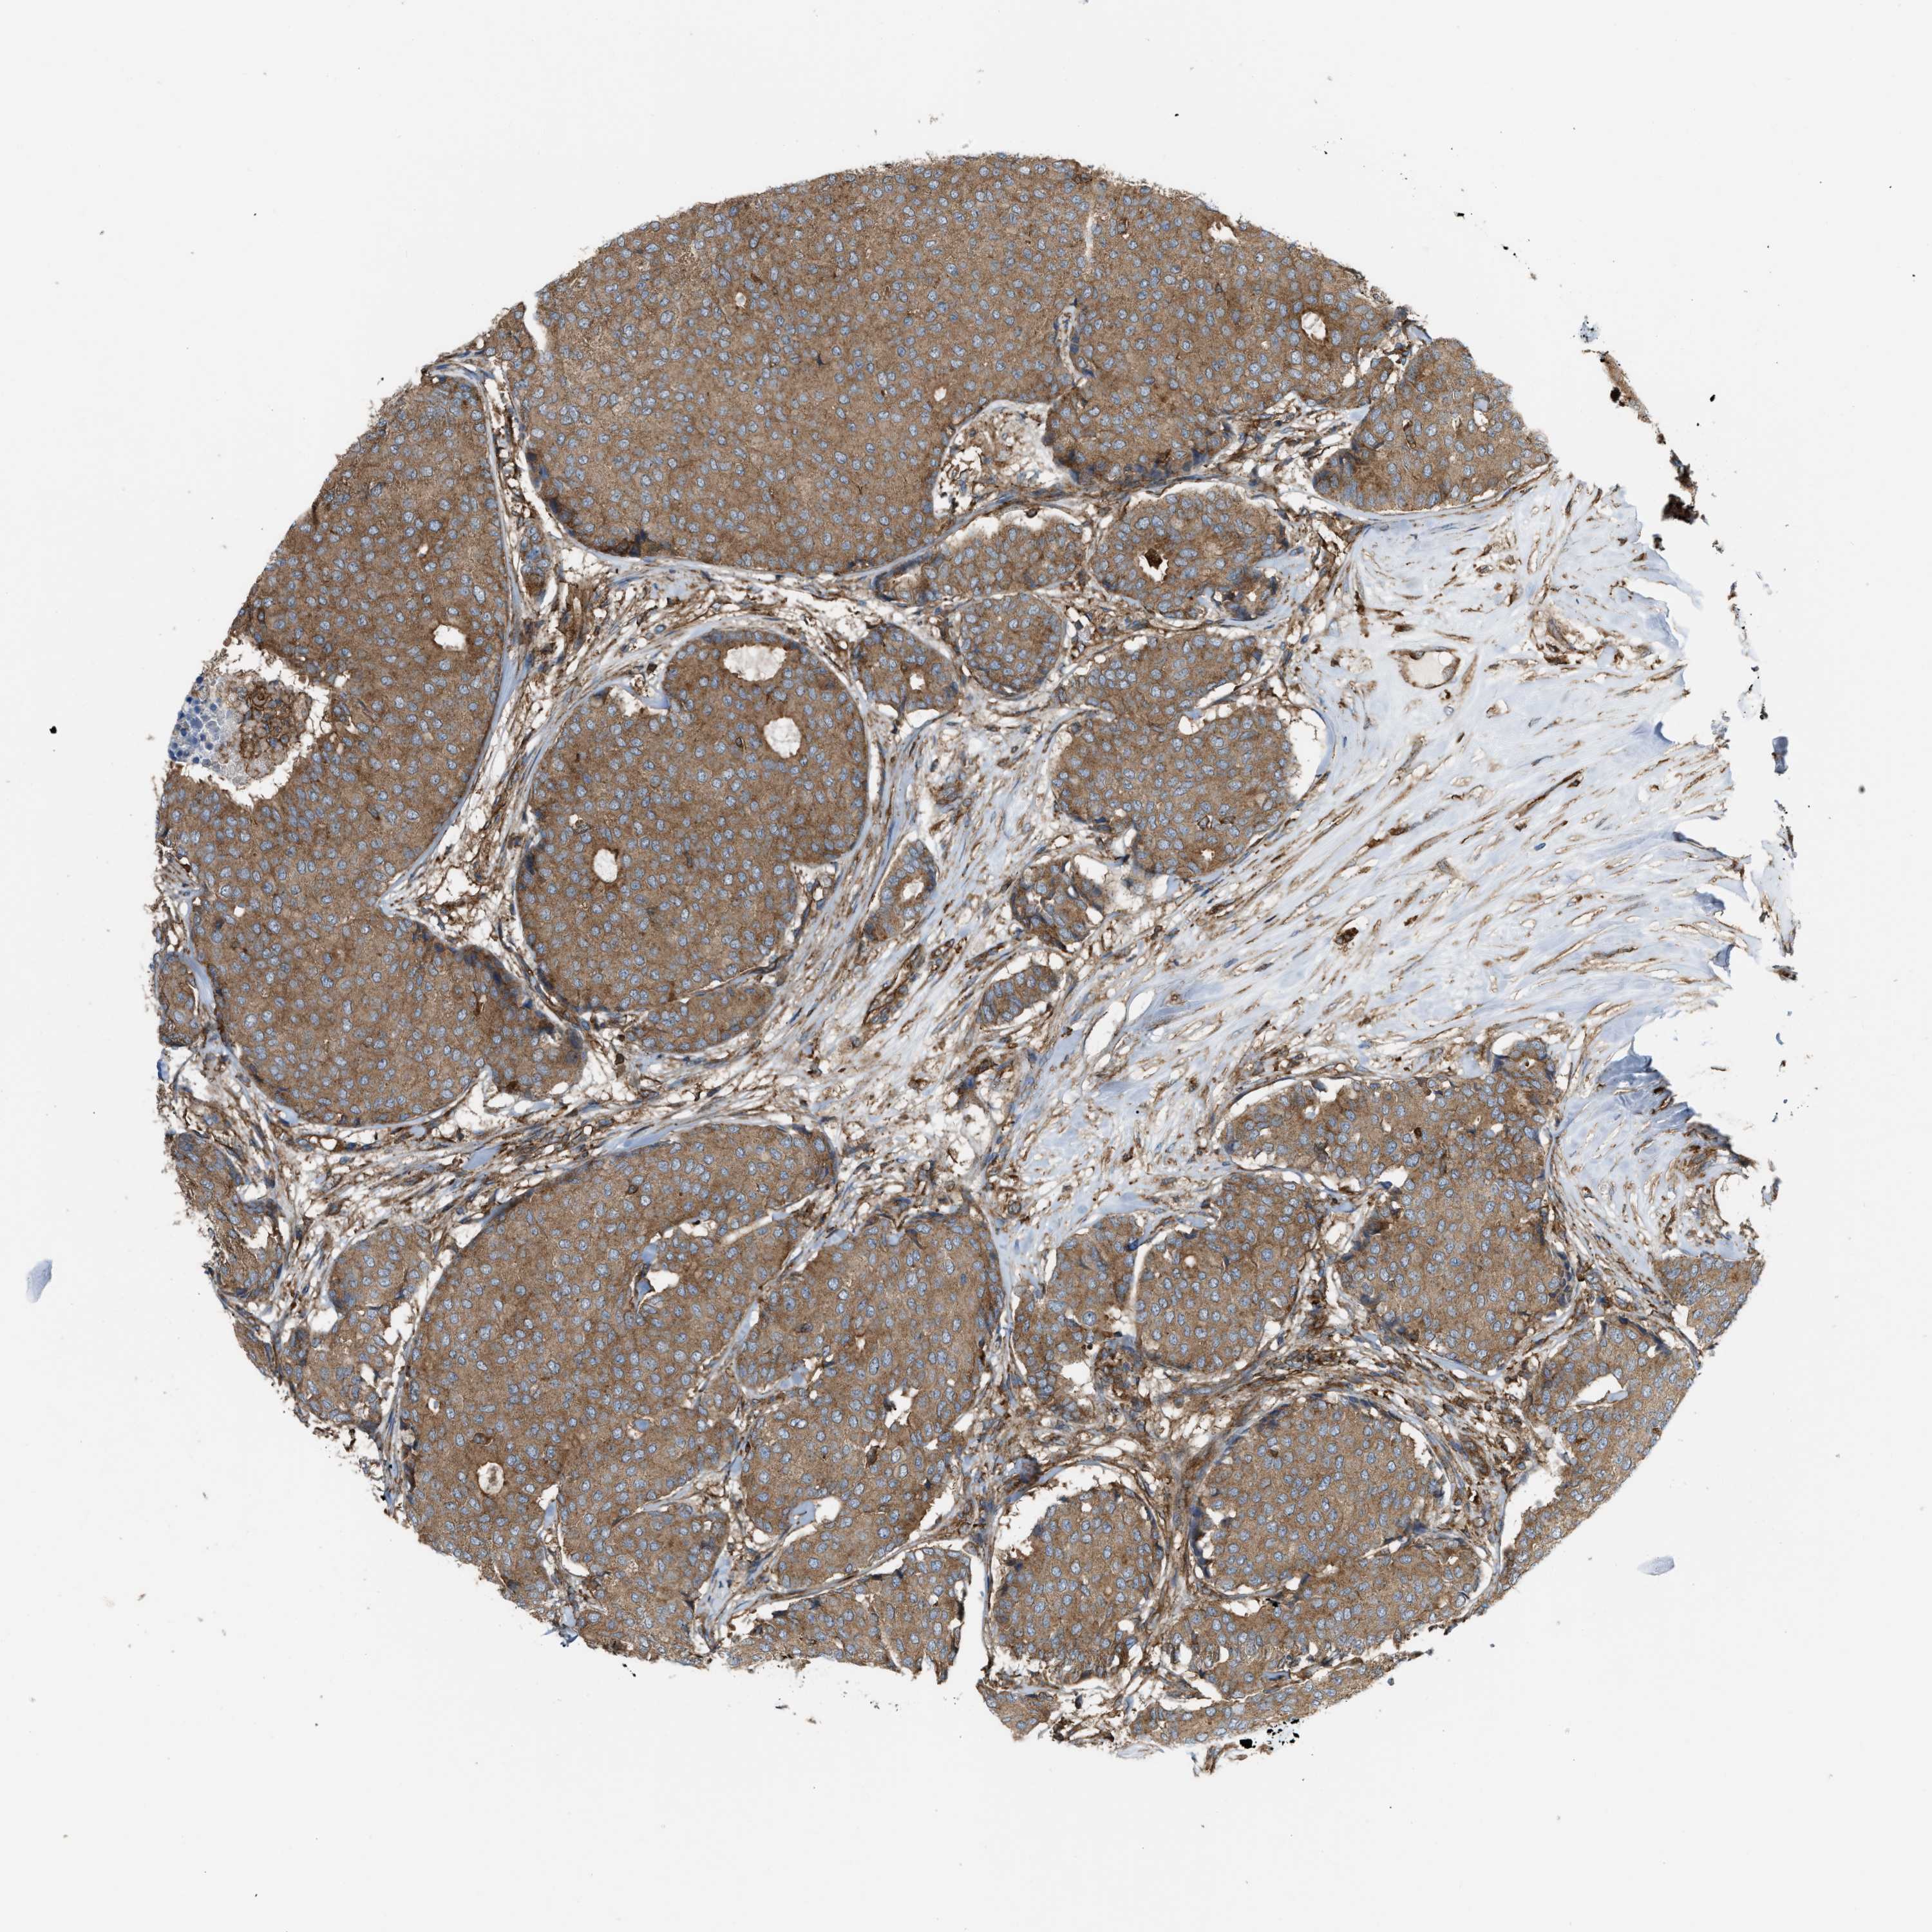

CANCER BREAST CANCER Show tissue menu

BRCA TCGA BRCA VALIDATION PROTEIN EXPRESSION